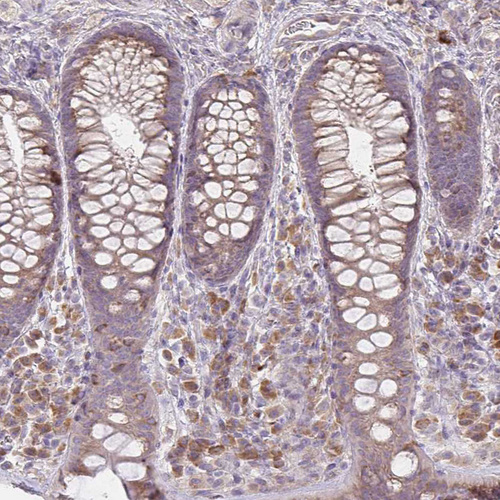

Immunohistochemical staining of human rectum shows weak cytoplasmic positivity in glandular and lymphoid cells.